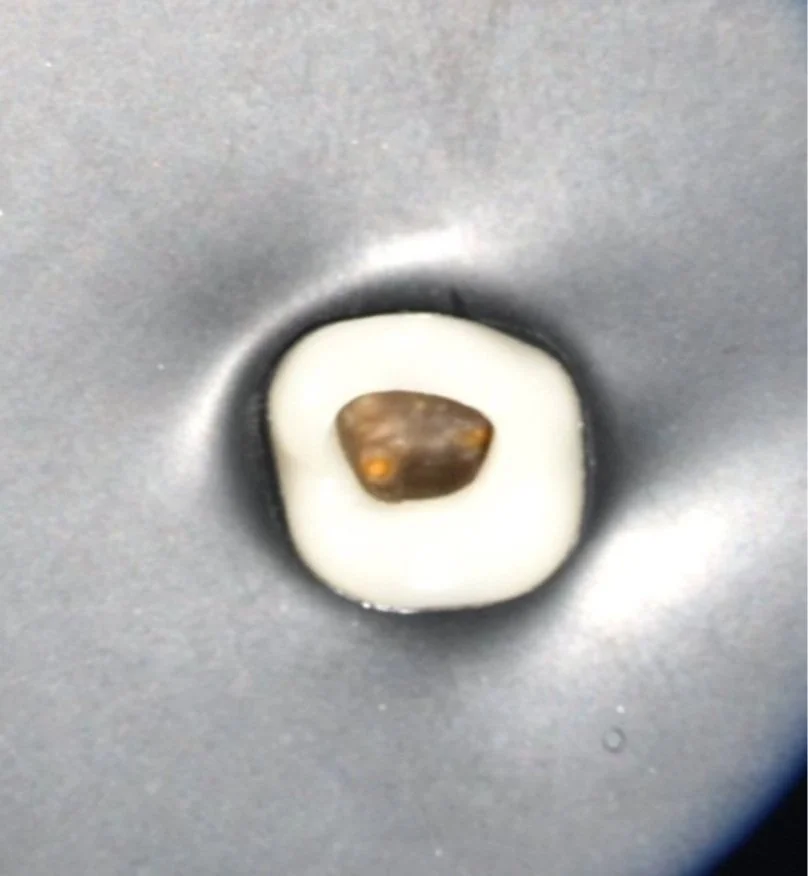

Ein Meilenstein ist die Verwendung des Dentalmikroskopes! Denn der perfekt ausgeleuchtete und maximal vergrößerte Zugang ermöglicht es uns, Strukturen zu entdecken und damit zu behandeln, die dem bloßen Auge bisher verborgen blieben.

+MEHR Technik: Mikroskop ZEISS PROergo

Kofferdam, eine Selbstverständlichkeit für jeden Endodontologen: Mit diesem kleinen, elastischen OP-Tuch schützen wir Ihren Zahn während der Behandlung vor dem Eintritt neuer Bakterien und Sie vor unseren Spüllösungen. Die Abschirmung des Umfeldes fördert eine präzise Fokussierung auf die Details.

+MEHR Methode: Absolute Trockenlegung